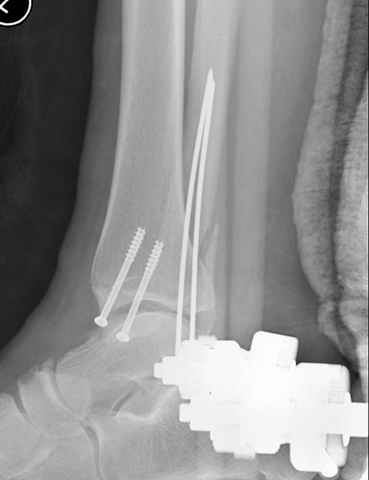

Второй случай сделан из одного разреза

Pilon fracture:

-Появляется ориентир и остов, на чем можно строить восстановление, почему сперва малоберцовую, впервые обьяснили и описали (Pylon type and Ankle fractures) в середине 50х Rienau и Gay.

Восстановливая длину и ротацию малоберцовой кости, затем относительно легче произвести реставрацию остальных элементов перелома дистального эпиметафиза болшеберцовой кости.

конец малоберцевой кости, к нему прикрепляется латеральный суставной фрагмент дистального эпиметафиза большеберцовой кости (как на снимке)

и таранная кость, которые при репозиции малоберцовой кости репонируются автоматически.

-Малоберцовую! Можно низвести аппаратом или пластиной.